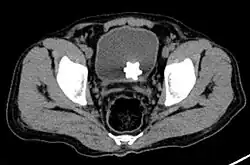

Large jackstone in the bladder of a 60-year-old man. Stone was removed by open cystolithotomy

Jackstone calculi are rare bladder stones that have an appearance resembling toy jacks. They are almost always composed of calcium oxalate dihydrate and consist of a dense central core and radiating spicules. They are typically light brown with dark patches and are usually formed in the urinary bladder and rarely in the upper urinary tract. Their appearance on plain radiographs and computed tomography in human patients is usually easily recognizable. Jackstones often must be removed via cystolithotomy.[10]